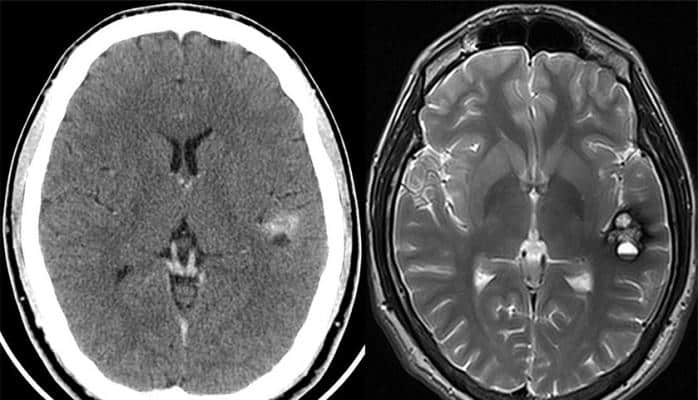

İsrailin “Zebra Medical Vision” şirkəti diaqnoz qoymaq üçün kompüter tomoqrafiyası, maqnit rezonans tomoqrafiyası və digər şəkillərin nəticələrini analiz edən “Zebra AI1” (və ya Zebra-Med) aparatını nümayiş etdirib. Robotun rəyi həkimlər tərəfindən son qərarın qəbul edilməsi üçün onlara təqdim olunur.

“ICTnews” Elektron Xəbər Xidməti “Hi-News” resursuna istinadən yazır ki, süni intellekt 11 müxtəlif xəstəliyi avtomatik müəyyənləşdirir, ilin sonunadək isə onların sayının 17-dək artırılacağı gözlənilir. Robotun aşkarlaya bildiyi patologiyalar arasında ağciyər xərçəngi, süd vəzi xərçəngi, ürək-damar xəstəlikləri, eləcə də baş-beyin travmaları qeyd edilir. Mütəxəssislər nümunə kimi tac arteriyalarında kalsiumun toplanmasının aşkarlanması üçün aparılan tədqiqatı göstərirlər.

Mütəxəssislərin sözlərinə görə, dərin kompüter təlimi sisteminin “öyrədilməsi” üçün layihə ilə əməkdaşlıq edən xəstəxanalar tərəfindən təqdim edilən çoxlu yüksək keyfiyyətli fotoşəkillərdən istifadə olunub. “Yüzlərlə kompüter tomoqrafiyası şəkli ilə keçirilən eksperimentdə süni intellekt 95 faiz düzgün qoyulmuş diaqnoz nəticəsi nümayiş etdirib. Bundan başqa, “Zebra AI1” ABŞ, Böyük Britaniya və digər ölkələrin tibb müəssisələrində istifadə edilən radioloji informasiya sistemləri (RIS) və fotoşəkillərin mübadilə sistemləri (PACS) ilə inteqrasiya edilib. “Zebra AI1” aparatı vasitəsilə bir müayinənin qiyməti 1 dollar təşkil edir”, - alimlər bildirib.